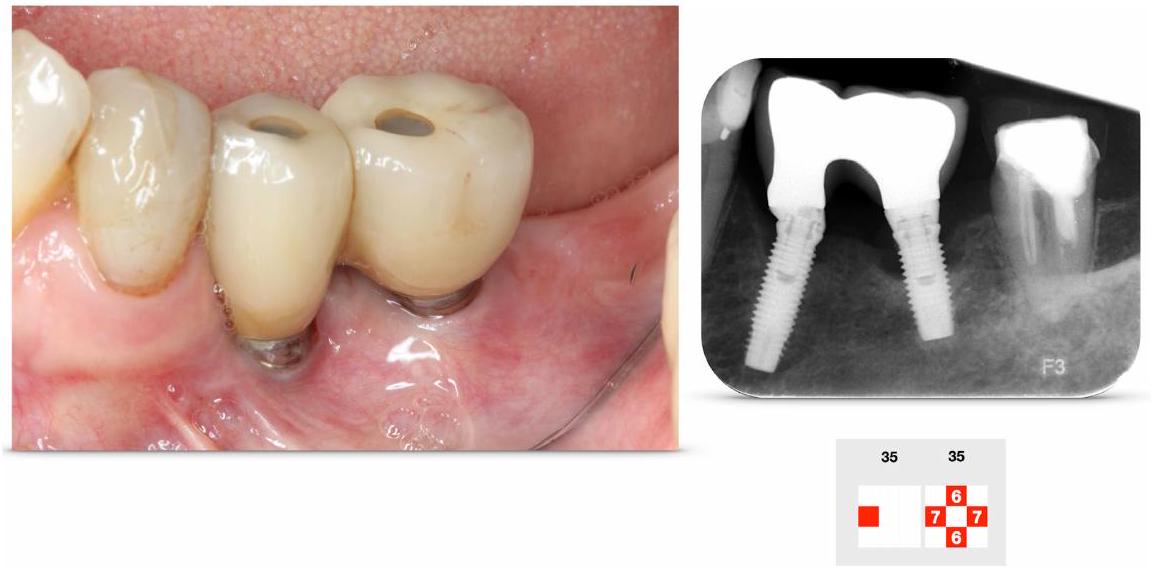

Peri-implantitis, a condition characterized by inflammation of the tissues surrounding dental implants, was first defined at the inaugural European Workshop on Periodontology. This condition poses significant challenges in dental practice due to its association with implant failure and the need for effective management strategies. The workshop aimed to establish a consensus on the diagnosis, etiology, and treatment of peri-implant diseases, highlighting the importance of understanding the biological and mechanical factors contributing to the condition.

Subsequent research has focused on identifying risk factors for peri-implantitis, including poor oral hygiene, smoking, and a history of periodontal disease. The findings underscore the necessity for regular monitoring and maintenance of dental implants to prevent the onset of peri-implantitis. Effective treatment protocols, including non-surgical and surgical interventions, have been developed, emphasizing the role of early detection and intervention in preserving implant health and longevity.

In the section on methods, the research examines the efficacy of various reconstructive techniques in treating peri-implantitis, aligning with existing periodontal literature. These techniques involve the application of bone replacement grafts, membranes, and bioactive agents to address bony defects resulting from disease. The primary goals of these methods include the regeneration of bony defects, re-osseointegration, and preservation of soft tissue height. Most studies reviewed are European, with many comparing reconstructive methods to access flap surgery, which serves as a control.

Despite the extensive evaluation of these techniques, systematic reviews indicate that reconstructive methods do not significantly improve primary outcomes such as probing pocket depth and bleeding on probing. For instance, a multicenter randomized controlled trial by Jepsen et al. found minimal differences in probing depth reduction between the control and test groups after 12 months. Similarly, other studies, including those by Renvert et al. and Derks et al., reported comparable outcomes between groups with and without reconstructive interventions. However, some studies noted improvements in radiographic parameters, suggesting potential benefits in bone level gain, although the clinical significance of these findings remains uncertain. Additionally, the impact of reconstructive measures on soft tissue levels has been infrequently assessed, with some evidence indicating less recession in test groups compared to controls.